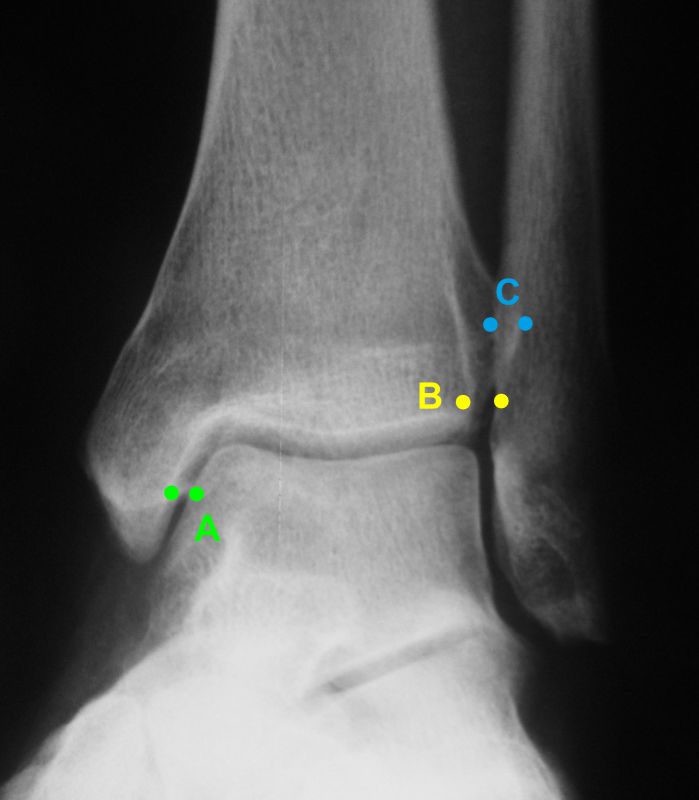

Röntgenaufnahmen dienen primär dem Ausschluss einer knöchernen Verletzung. Die Beurteilung der Geometrie der Malleolengabel kann einen ersten Hinweis auf eine Syndesmosenverletzung liefern. Die notwendigen Röntgenaufnahmen umfassen das Sprunggelenk anterior-posterior, lateral und in 20° Innenrotation (Mortise view). Zur Beurteilung der Syndesmose sind verschieden Parameter in der Mortise view beschrieben. Zu diesen zählen der tibiofibulare Clearspace, der mediale Clearspace, sowie die Überlappung der distalen Fibula und Tibia im Bereich der Incisura (Abbildung 2). Der Tibiofibulare Clearspace wird als verlässlichster Indikator für eine Syndesmosenverletzung gesehen, da er nicht signifikant von der tibialen Rotation beeinflusst wird 32. Er wird 1 cm proximal des Tibiaplafonds gemessen und sollte weniger als 6mm betragen 33. Jede Messung, die diesen Wert übersteigt, stellt einen Hinweis für eine Syndesmosenverletzung dar. Eine tibiofibulare Überlappung von 6 mm oder mehr in der AP Aufnahme, sowie mehr als 1 mm in der Mortise View Aufnahme gelten als physiologisch 33. Der mediale Clearspace sollte nicht mehr als 4 mm betragen 34.

Abbildung 3 zeigt ein Sprunggelenk nach Syndesmosenverletzung mit einem erweiterten Tibiofibularen Clearspace.